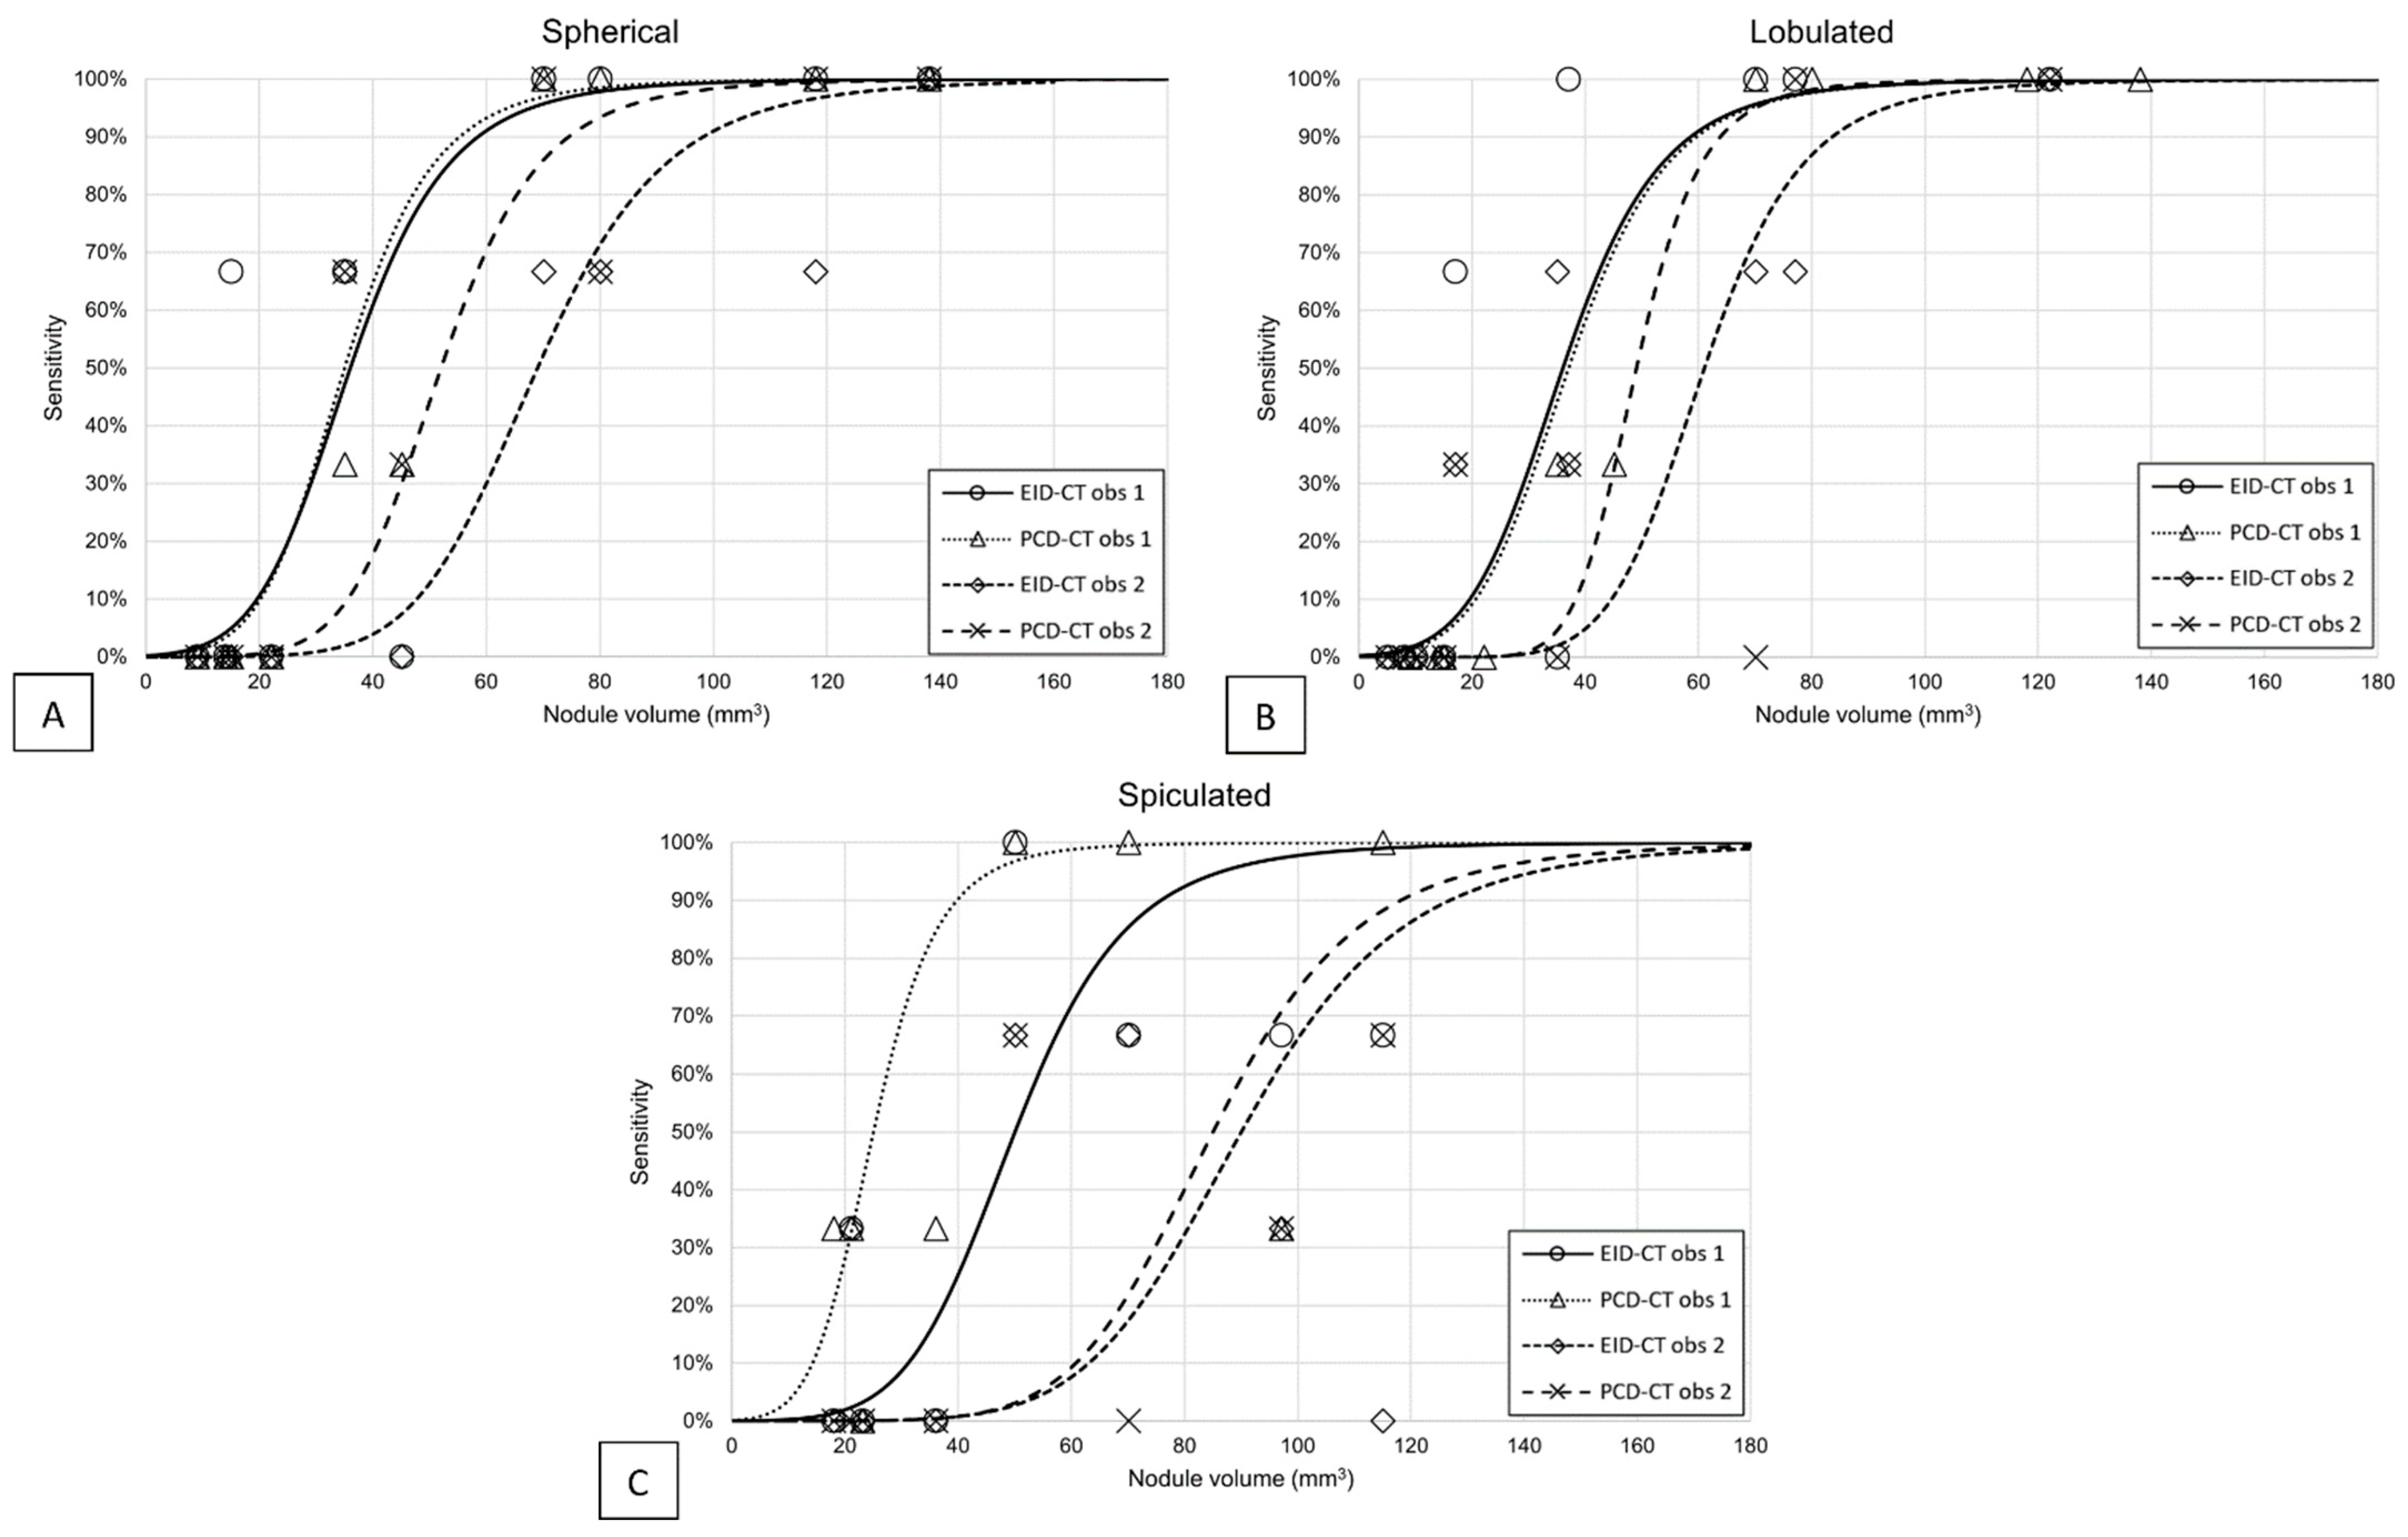

3.1. Detectability

- Xie, X.; Willemink, M.J.; de Jong, P.A.; van Ooijen, P.M.A.; Oudkerk, M.; Vliegenthart, R.; Greuter, M.J.W. Small irregular pulmonary nodules in low-dose CT: Observer detection sensitivity and volumetry accuracy. AJR Am. J. Roentgenol. 2014, 202, W202–W209. [Google Scholar] [CrossRef]